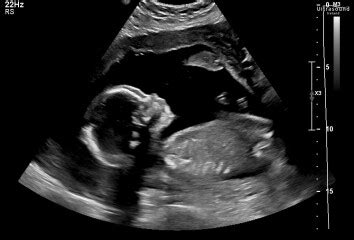

The 20-week anatomy scan , often simply called the mid-pregnancy scan or morphology scan , is a truly pivotal point in your prenatal care, especially here in South Africa . This isn’t just a quick peek; it’s a comprehensive, high-resolution ultrasound examination performed usually between 18 and 22 weeks of gestation . The primary purpose of this scan is to thoroughly assess the fetal anatomy, growth, and development, ensuring that everything is progressing as it should be. Think of it as your baby’s first really detailed health check-up, all while they’re still comfy inside you! During this scan, the sonographer or obstetrician will meticulously examine every major organ and body part of your developing baby. They’re looking at the brain, heart (checking all four chambers and major blood vessels – a super important part!), spine, kidneys, bladder, stomach, limbs, and even tiny fingers and toes. They’ll also measure various parts of your baby to ensure they’re growing at an appropriate rate, which helps confirm your estimated due date. Beyond just the baby, the sonographer will also assess other crucial elements of your pregnancy. This includes checking the position and health of the placenta, measuring the amount of amniotic fluid surrounding your baby, and evaluating the cervix. These factors are all vital for a healthy pregnancy and can flag potential issues early on. For instance, a low-lying placenta (placenta previa) or insufficient amniotic fluid might require further monitoring. So, as you can see, this scan is incredibly comprehensive. It’s designed to pick up any significant structural anomalies or developmental issues that might affect your baby’s health. While it can detect a large percentage of major abnormalities, it’s important to remember that no scan is 100% foolproof, and some conditions simply cannot be seen or develop later. However, for many families in South Africa , this scan provides immense reassurance, confirming that their little one is thriving. It’s also often the moment many parents find out the sex of their baby, if they choose to know, adding another layer of excitement to this significant appointment. So, when you walk into that ultrasound room, know that you’re not just seeing a cute picture; you’re getting a vital health assessment that empowers both you and your healthcare team to provide the best possible care for your pregnancy journey. This thorough examination is a cornerstone of modern prenatal care and an invaluable tool for ensuring the well-being of both mother and baby throughout the remainder of the pregnancy, and even preparing for birth and beyond here in South Africa .